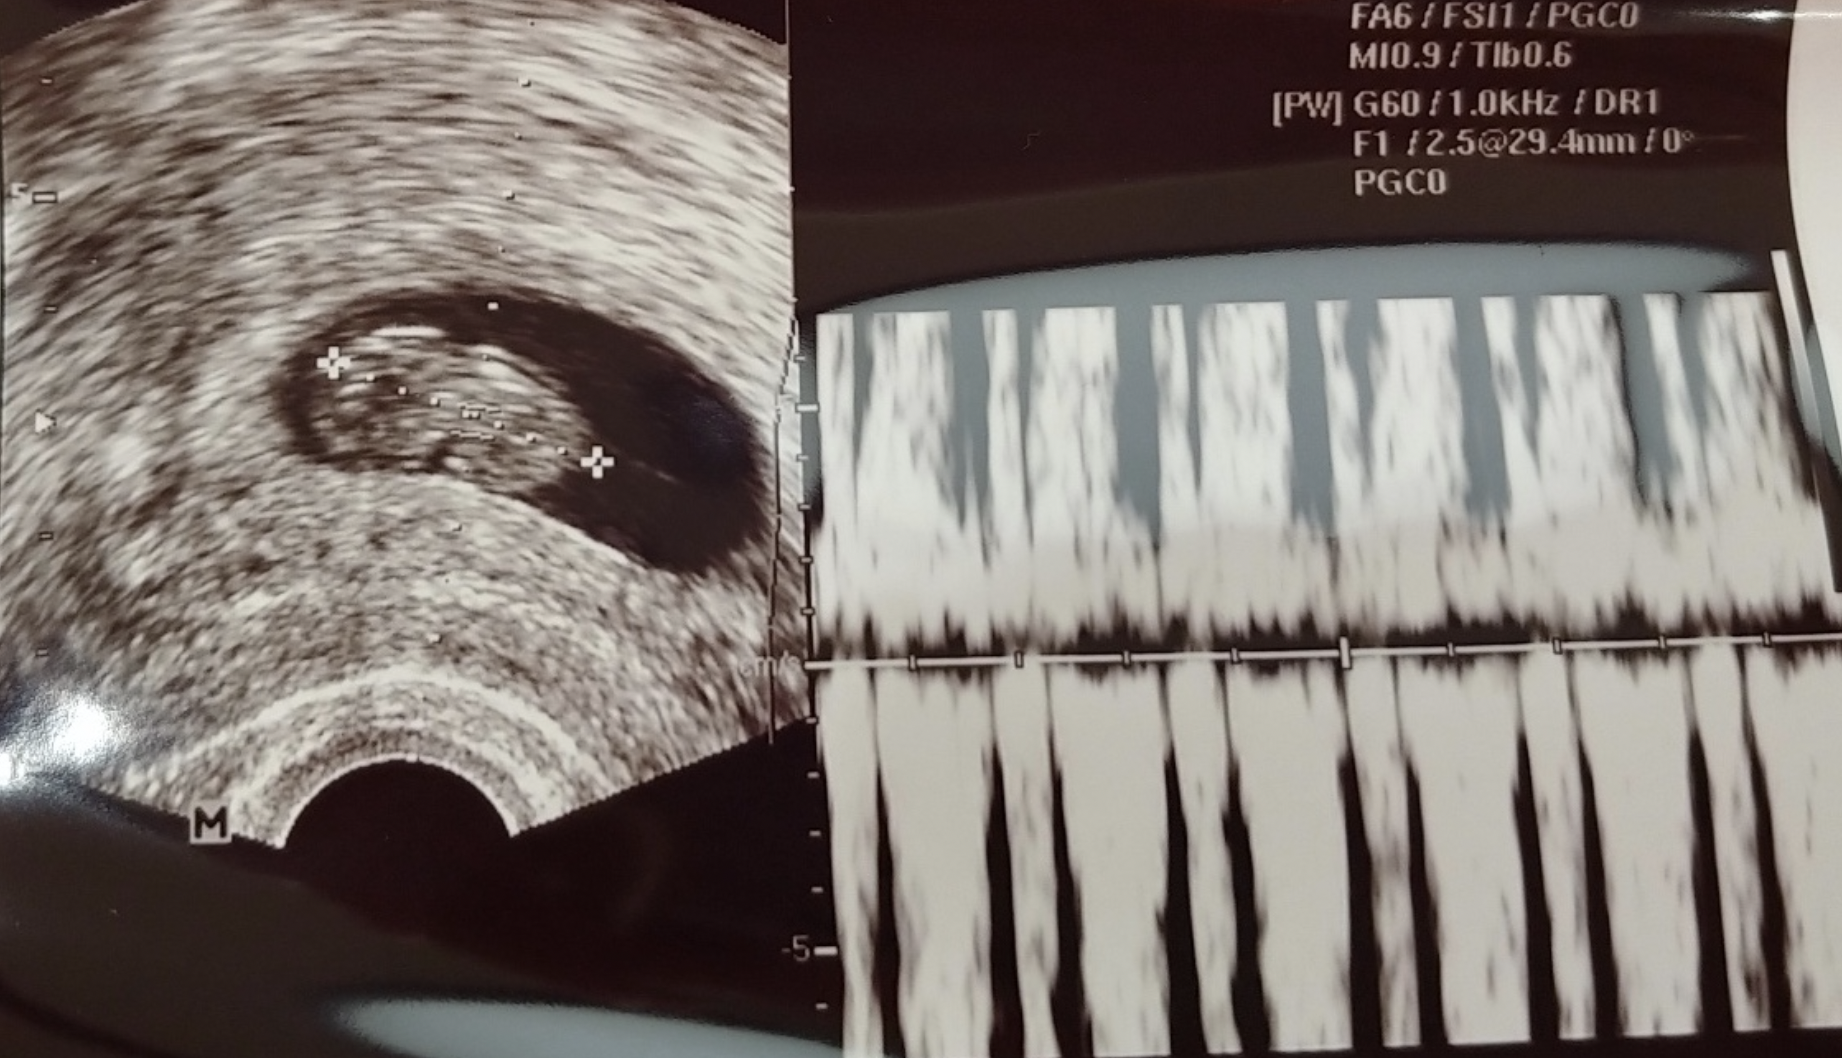

이후의 기억은 정확하지는 않지만, 일주일 쯤 후 다시 피검사를 해서 수치가 많이 올라갔는지 확인했고 결과가 괜찮았다. 그리고 또다시 2~3주쯤 지나 아기집과 난황을 확인했고, 2주쯤 후인 6월 18일에 초음파 진료를 통해 태아도 보고 태아의 심장소리를 들을 수 있었다. 난임 전문병원으로는 이제 그만 오고, 다니기 편한 산부인과를 선택해서 이제 그쪽으로 다니라고 했다.

태아와 태아의 심장소리 반응형'끄적끄적' 카테고리의 다른 글